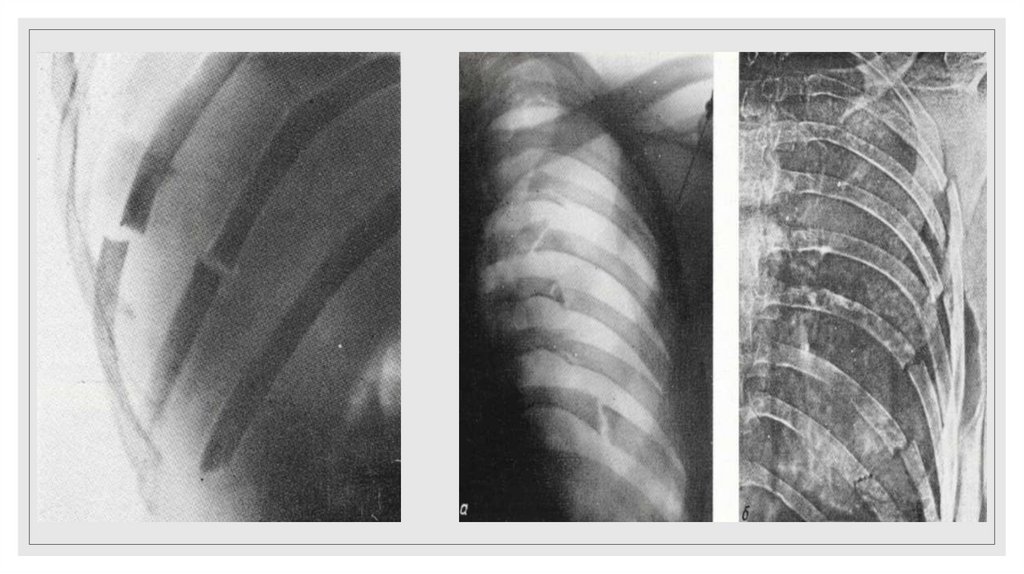

Повреждение грудного отдела аорты

25. Рентгенодиагностика переломов ребер основывается на определении линии перелома и смещении отломков. Косвенным признаком

повреждения ребер является

наличие параплевральной гематомы, имеющей полуовальную форму и

располагающейся вдоль внутренней поверхности ребер на уровне их повреждений

или несколько ниже.

◦ Важно помнить, что на стандартных прямых рентгенограммах видны ребра до VIII

включительно.

◦ Переломы нижних ребер могут сочетаться с повреждением органов брюшной

полости (печень, селезенка).

◦ Чаще всего на стандартных прямых рентгенограммах не диагностируются

переломы боковых отрезков без смещения отломков либо с незначительным

смещением отломков.

◦ Необходимо тщательно изучать не только ребра, но остальные кости (ключицы,

лопатки, позвоночник, а так же грудину)